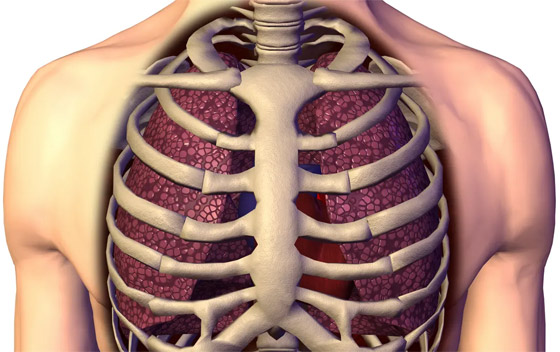

يمكن دراسة الأدوية وآليات المرض واختبارها على هذه النماذج المطبوعة في المختبر، عوضاً عن الحيوانات. وقال شرزانوفسكي: "لم يشارك في هذه الندوة أكثر من ثلاثة أشخاص، والجميع أخبروني بأنني لن أنجح أبداً". لكن في شهر أبريل/نيسان، نشر شرزانوفسكي وزملاؤه ورقة بحثية عن تقنية أكثر تطوراً حتى من الطباعة الحيوية. فقد نجحوا في تطوير نموذج لرئتين مطابقتين للرئتين البشريتين في مختبرهم في معهد نانو بجامعة سيدني، حيث يشغل شرزانوفسكي حالياً منصب نائب المدير. وتشرح ورقتهم البحثية طريقة تصنيعها.

كيف تبدو الرئة المستنسخة؟

الرئتان اللتان يبلغ عرضهما بضعة ملليمترات فقط، تشبهان رئتي البشر بدرجة طفيفة. وهما موضوعتان في أنبوب بلاستيكي، وعند النظر إلى داخل هذا الأنبوب من أعلى، تبدوان مثل قطعة هلام صغيرة تنتشر في غشاء رقيق. حيث قال شرزانوفسكي: "من الضروري أن نتأكد من نمو الرئتين بما يكفي لتكونا جاهزتين وناضجتين للتجارب، لذلك طوّرنا أقطاباً كهربائية توضع باستمرار فوق نماذج الرئتين، وتراقب الإشارات الكهربية الحيوية لهما".

أُجريت محاولات أخرى لبناء رئات معملية، لكن شرزانوفسكي يقول إنها بسيطة جداً، وثابتة جداً، لكن رئة الإنسان تتغير وتتوسع وتتحرك باستمرار، بسبب تأثير الدورة الدموية وضربات القلب، على سبيل المثال. الفرق بين هذه النماذج البسيطة والرئتين اللتين صنعهما شرزانوفسكي، صاحب الفكرة، وتلميذته في الدكتوراه ثانه هوين فان، التي أسهمت بدور أساسي في تصميمها وبنائها، هو أنها تتضمن هذه الحركة الفسيولوجية للسوائل في الخلايا.

يقول شرزانوفسكي: "بدأنا في بناء هاتين الرئتين حرفياً خلية خلية، لنجعلها أقرب ما يمكن إلى فسيولوجية رئتي الإنسان. وهذا ما يجعل نموذجنا فريداً من نوعه. والميزة الأخرى لنموذجنا هي أنه يمكننا أخذ خلايا من مرضى مختلفين، وإضافتها إلى هاتين الرئتين لتجربة العلاجات المخصصة".

أضاف: "وميزة أخرى نفتخر بها هي الحجم. فالكثير من النماذج صغيرة جداً، لدرجة أنه لا يمكنك إجراء تجارب كثيرة على نفس النموذج، لكن نموذجنا كبير نسبياً، وهذا يعني أنه يمكننا مراقبة الاستجابات المناعية، والأهداب، وإفراز المخاط، وكل ذلك في نموذج واحد".